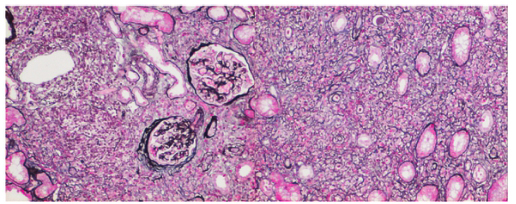

对外院的肾标本进行重新制片、免疫组化及病理会诊:肾小球缺血皱缩,肾小管弥漫萎缩及消失,肾间质大量淋巴、浆细胞浸润伴纤维化,呈“席纹”征,小动脉管壁增厚(图1,图2A)。浆细胞中IgG4阳性细胞>10/HPF,占IgG阳性细胞比例大于40%(图2B),考虑IgG4相关性间质性肾炎。

图1 IgG4相关性间质性肾炎:肾小球轻度缺血性皱缩,肾小管萎缩,肾间质大量细胞浸润(PASM×200)